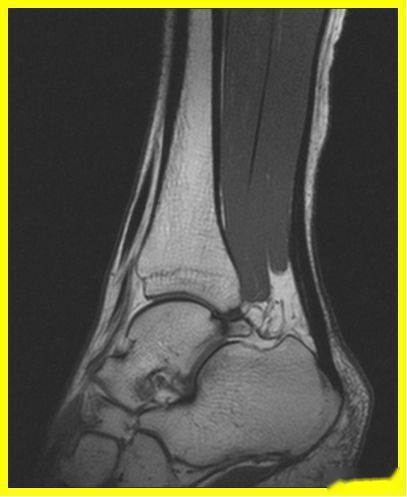

mri可现实跟腱腱鞘周围肿胀,退行性变和跟腱大片撕裂.